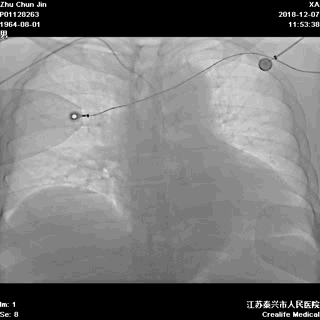

胸部透视,看看心影吧:

▲胸部透视见纵隔影似乎明显增宽!是夹层吗?

接下来是经猪尾导管行主动脉造影,还是行其它检查呢?